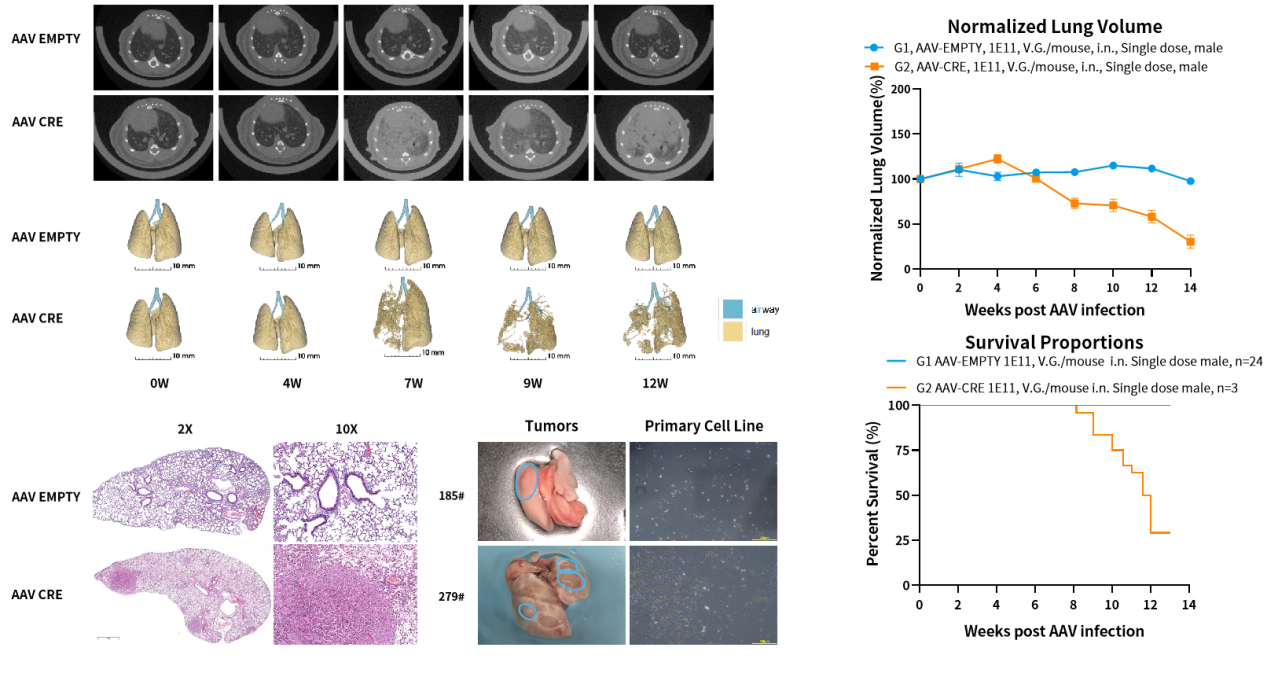

Stk11/EGFP/Kras-LSL-G12D小鼠是一种原发肺癌小鼠模型,包含Kras基因突变与STK11蛋白缺失。STK11突变在非小细胞肺癌(NSCLC)中发生率超过10%;Kras 突变在肺癌占34%,以NSCLC占比较多,肺鳞癌中占比较少。该模型Kras突变上游含有lox-stop-lox终止序列,在没有Cre重组酶的条件下不表达;Stk11也需要Cre的存在才能发生敲除。因此,使用AAV-CRE对小鼠进行诱导,即可使其产生肿瘤。

图1 Stk11/EGFP/Kras-LSL-G12D原发肺癌小鼠模型可通过AAV-CRE诱导引发肺癌。

图2. Stk11/EGFP/Kras-LSL-G12D瘤块来源细胞系皮下移植造模的抗肿瘤药效评价。

图3. Stk11/EGFP/Kras-LSL-G12D瘤块来源细胞系原位移植造模的抗肿瘤药效评价。